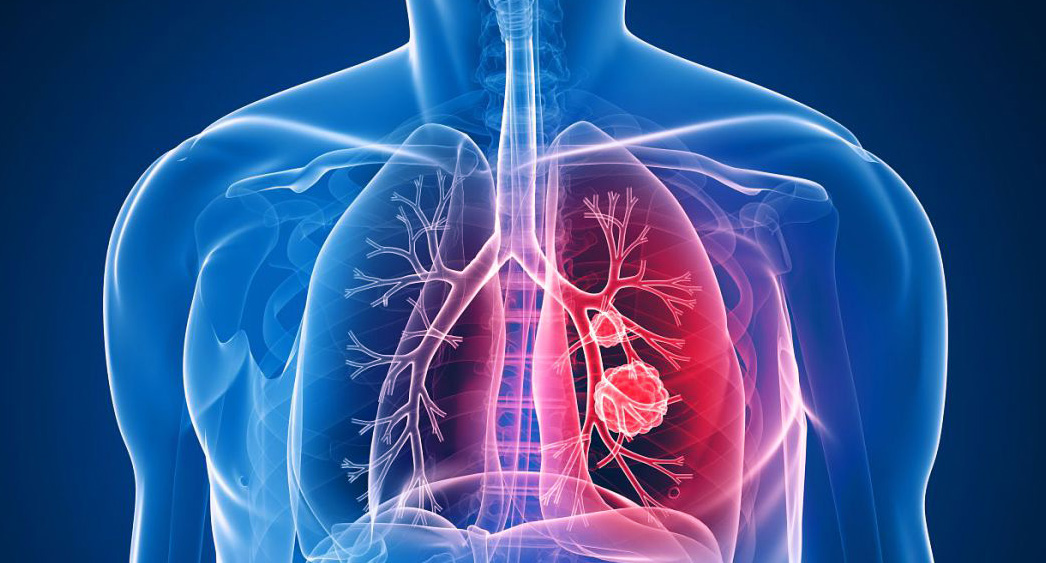

폐암은 원발성 폐암을 말하며 원발성 폐암은 폐에서 기원하는 악성 종양을 말한다. 폐로 전이된 암은 폐로 전이된 것으로 분류되며, 폐암이라기 보다는 기원 장기로 전이된 것으로 분류된다. 폐암은 조직학적 유형에 따라 크게 소세포폐암과 비소세포폐암으로 분류된다.

이 분류의 이유는 소세포 폐암이 치료 및 예후 측면에서 다른 유형의 폐암과 확연히 다른 특징을 가지고 있기 때문입니다.